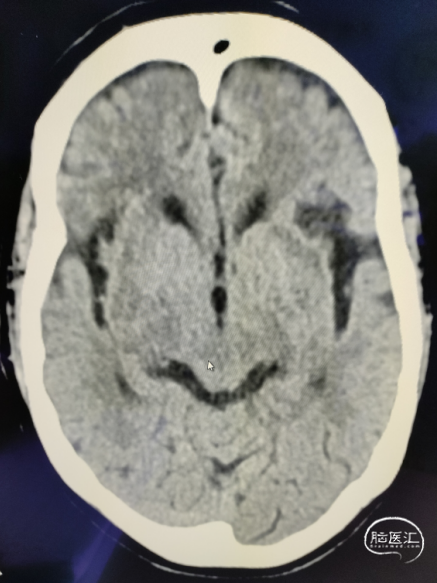

手术过程

出院时情况

术中

路径困难是导致困难取栓的常见原因之一,既往因为普通导引导管较硬而无法通过迂曲血管到达目标血管,并增加手术时间。同时既往中间导管通过性能差而无法顺畅的实现高到位并进行抽吸,两者大大降低了取栓效率。普微森MidAccess™导引导管 088-90 cm具有8F普通导引导管直径,通过性能明显优于普通导引导管,特别是在该病例RCCA如此迂曲的情况下,仅在泥鳅导丝引导下就可以顺利通过Z字型迂曲到达C1段,为后续068中间导管提供了有力支撑并缩短的取栓距离。普微森MidAccess™导引导管 068-132 cm具有口径大、高到位、耐疲劳的特点,在微导管微导丝引导下3次顺利通过眼动脉段并送至RMCA起始段及M1中远端进行抽吸,不仅缩短了取栓时间,也避免了反复支架取栓对血管管壁的损伤。